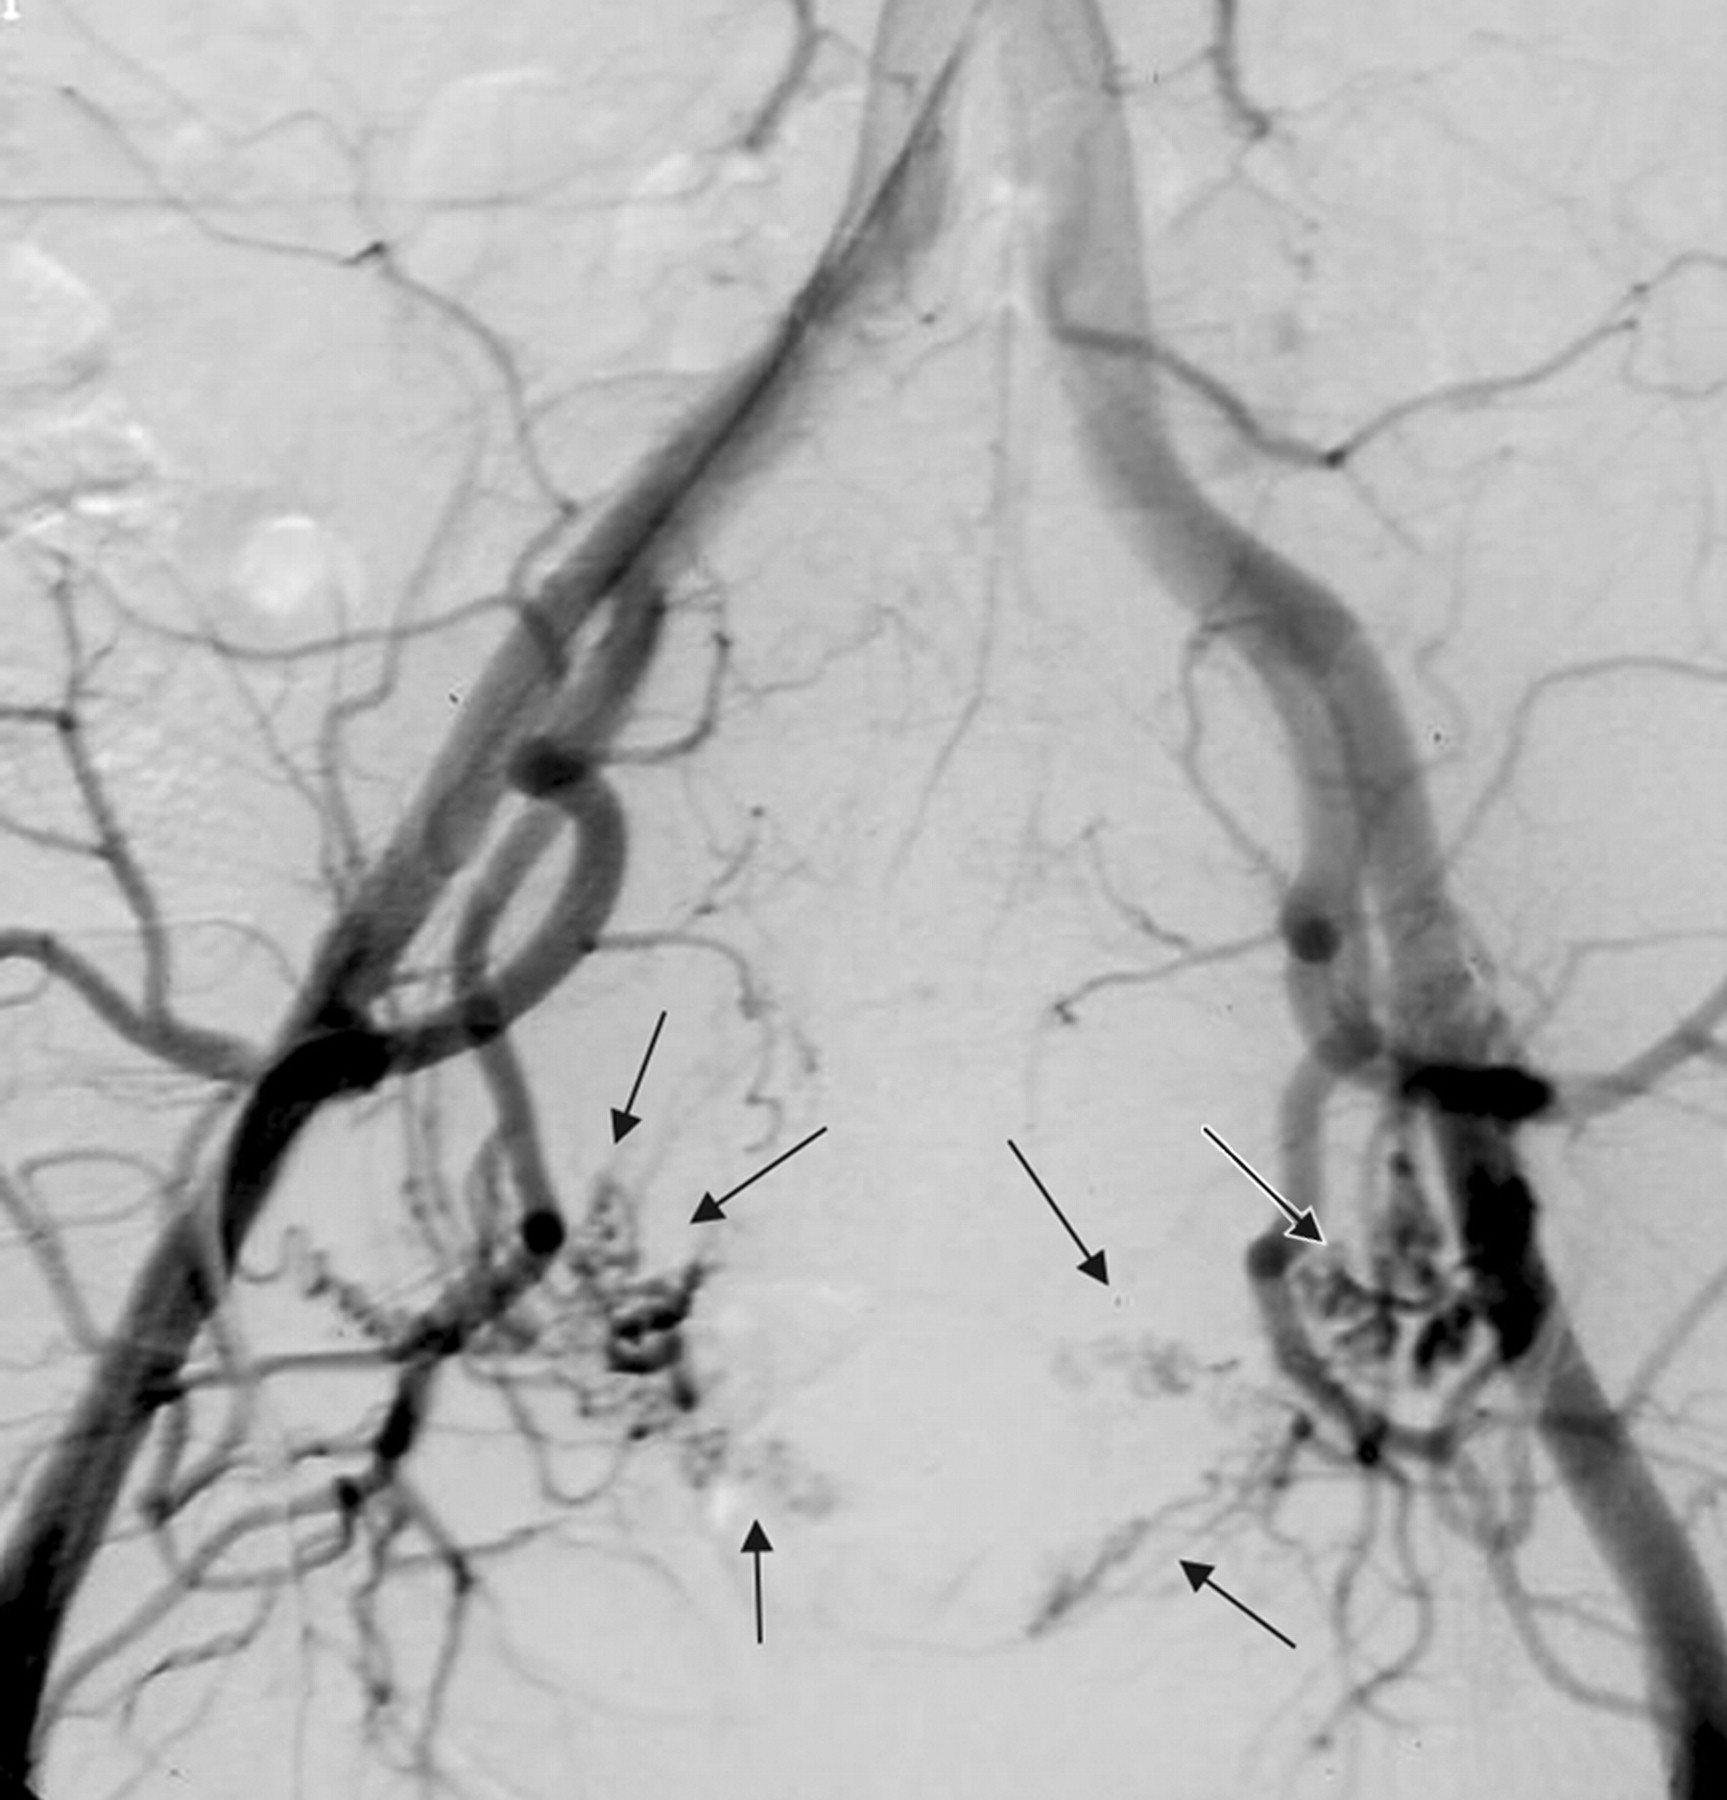

• Aorta -> Common Iliac -> Internal Iliac -> Anterior Division -> Uterine Artery

• Uterine artery embolization is introduced in the 1970s as a life-saving procedure to control intractable postpartum hemorrhage as an alternative to emergency hysterectomy

• In a landmark 1995 paper in The Lancet, French gynecologist Dr. J.H. Ravina and his IR colleagues proposed that if embolization could safely control acute hemorrhage, it could probably also be used to cut off blood supply to hypervascular fibroids.